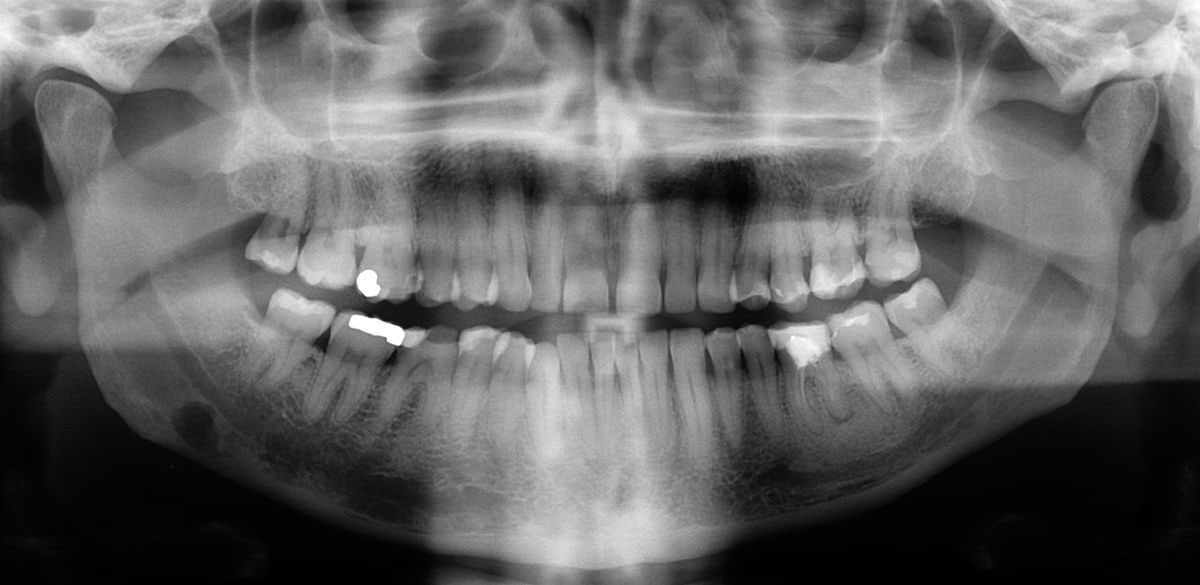

A panoráma felvétel segít a fogorvosnak megállapítani a látható jelek nélküli fogszuvasodást, fertőzést, csontveszteséget, fogágypusztulás mértékét. Felnőtteknél megállapítható a bölcsesség fog elhelyezkedése az állcsontban. Gyerekeknél a fogröntgen megmutathatja, hogy hol vannak a maradó fogak és azoknak számát. Góckutatás esetén elengedhetetlen.

A panoráma felvétellel átfogó két dimenziós képet lehet kapni az alsó- felső állcsontról, a bennük futó képletekről, a fogak helyzetéről, állapotáról illetve az állkapocsízületről.